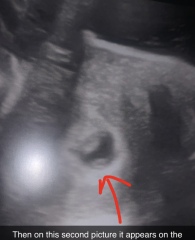

I went for a scan at 7w and 6d and I don’t know if I’m just over thinking it but it looks like there is two babies, I just want to know what everyone else’s thoughts are?

Isn't that the yolk sac?

I think that’s a yolk sac

I believe the sonographer would have been very sure if it was twins at this stage. My 7 week twin scan was very clear

No, it's the yolk sac.